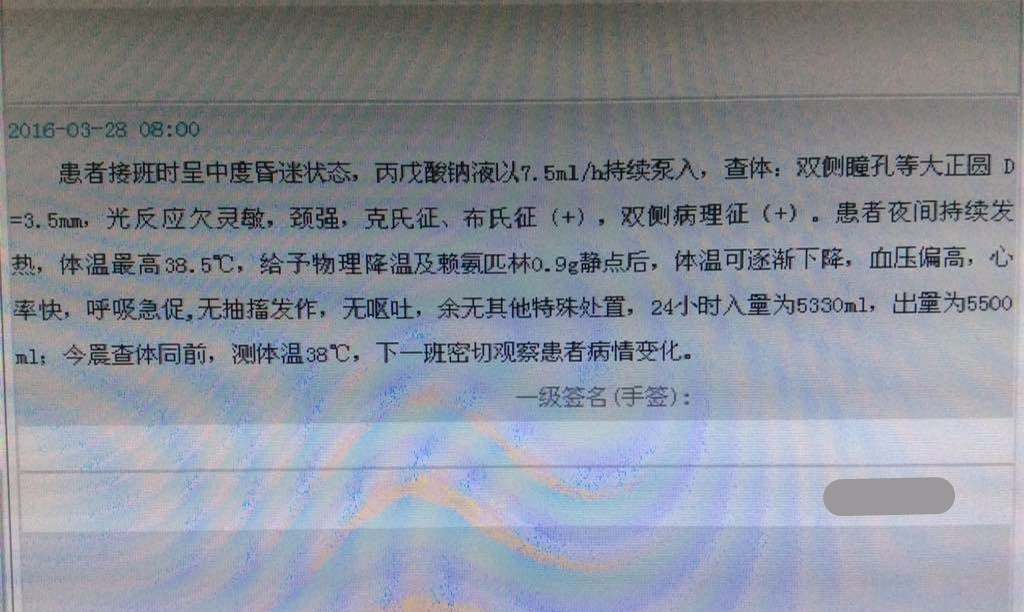

脑脊液细菌培养阴性,今天口唇又出现疱疹了,但脑脊液不支持病毒,不过有时候化验也有误差,加强抗生素的话用啥好呢?M老师?

要兼顾阳性和阴性菌,要头孢三代的,最低也是罗氏芬。